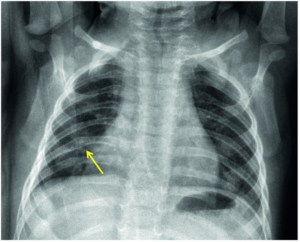

The diagnosis of bronchiolitis is clinical (based on the patient’s history and physical examination). Laboratory testing and radiographic studies are not recommended for diagnosis. CBC, inflammatory markers, blood culture, and chest x-ray should only be used when a serious bacterial infection (SBI) is suspected. A viral respiratory panel may be used to aid in the more accurate diagnosis of the viral pathogen, which may be useful for the hospitalized patient or in patients not following the expected course of illness. A chest x-ray may be performed to rule out conditions like effusions or pneumothorax when there is clinical suspicion but should not be used to evaluate for pneumonia as that is a clinical diagnosis. In bronchiolitis, the chest x-ray may show hyperinflation of the lungs, atelectasis, or peribronchial cuffing that is often referred to as the classic cheerio (see CXR).